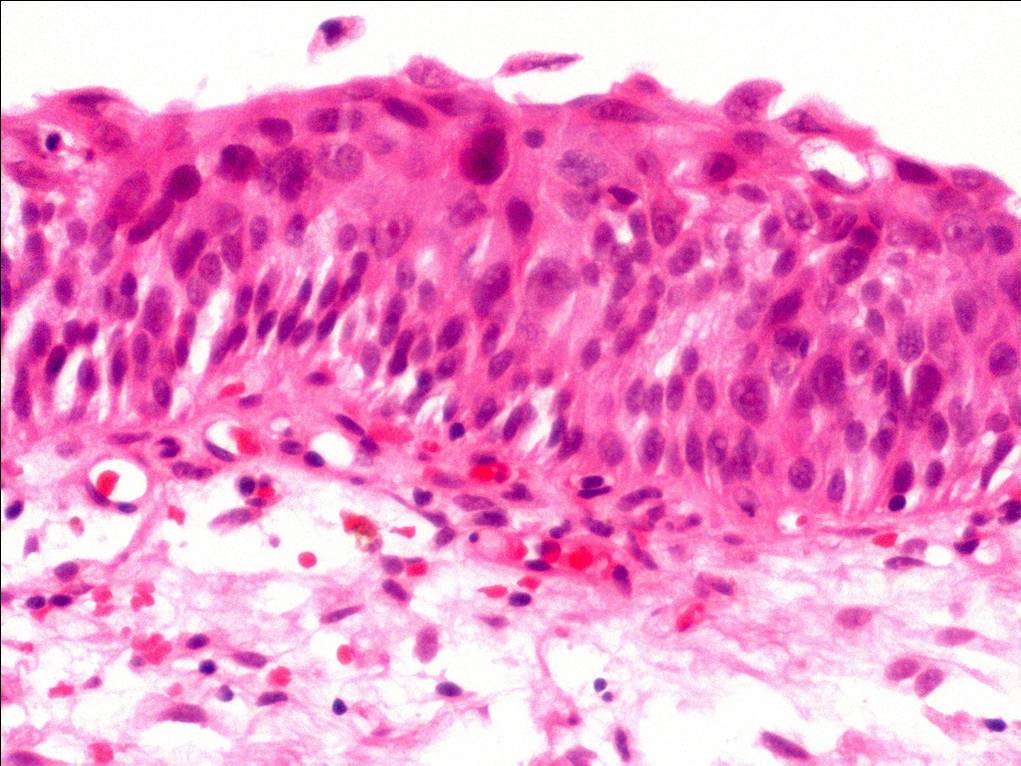

Bladder Flat Lesions

Case ID: 73